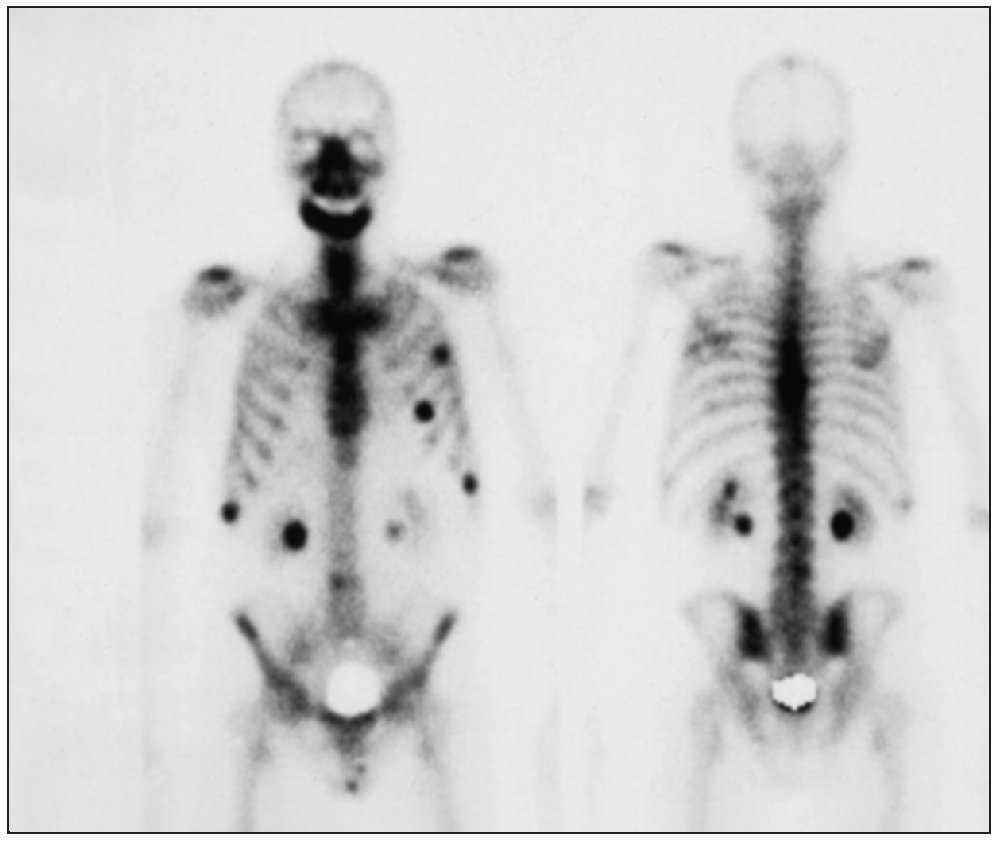

Los tumores pueden provocar metástasis en los huesos. Las metástasis óseas son especialmente frecuentes en los carcinomas de mama, próstata, pulmón y vejiga urinaria, así como en el mieloma múltiple (fig. 1). Las metástasis en sí provocan una afectación ósea relativamente insignificante, pero son productoras de mediadores parecidos a la parathormona que inducen una reabsorción de hueso. Este cuadro se asocia a dolor intenso y afecta gravemente a la calidad de vida del paciente. La causa es la secreción de sustancias algésicas (inductoras de dolor) por el tumor, la presión creciente sobre los tejidos circundantes como resultado del crecimiento tumoral y también la distensión del periostio rico en terminaciones sensitivas. Existe además el riesgo de aparición de fracturas óseas y de compresiones nerviosas, sobre todo en la columna vertebral, con las parálisis consiguientes.

Figura 1. Gammagrafía en una paciente con metástasis óseas múltiples y osteonecrosis mandibular asociada a bifosfonatos (misma paciente que en las figuras 5a a 5c).